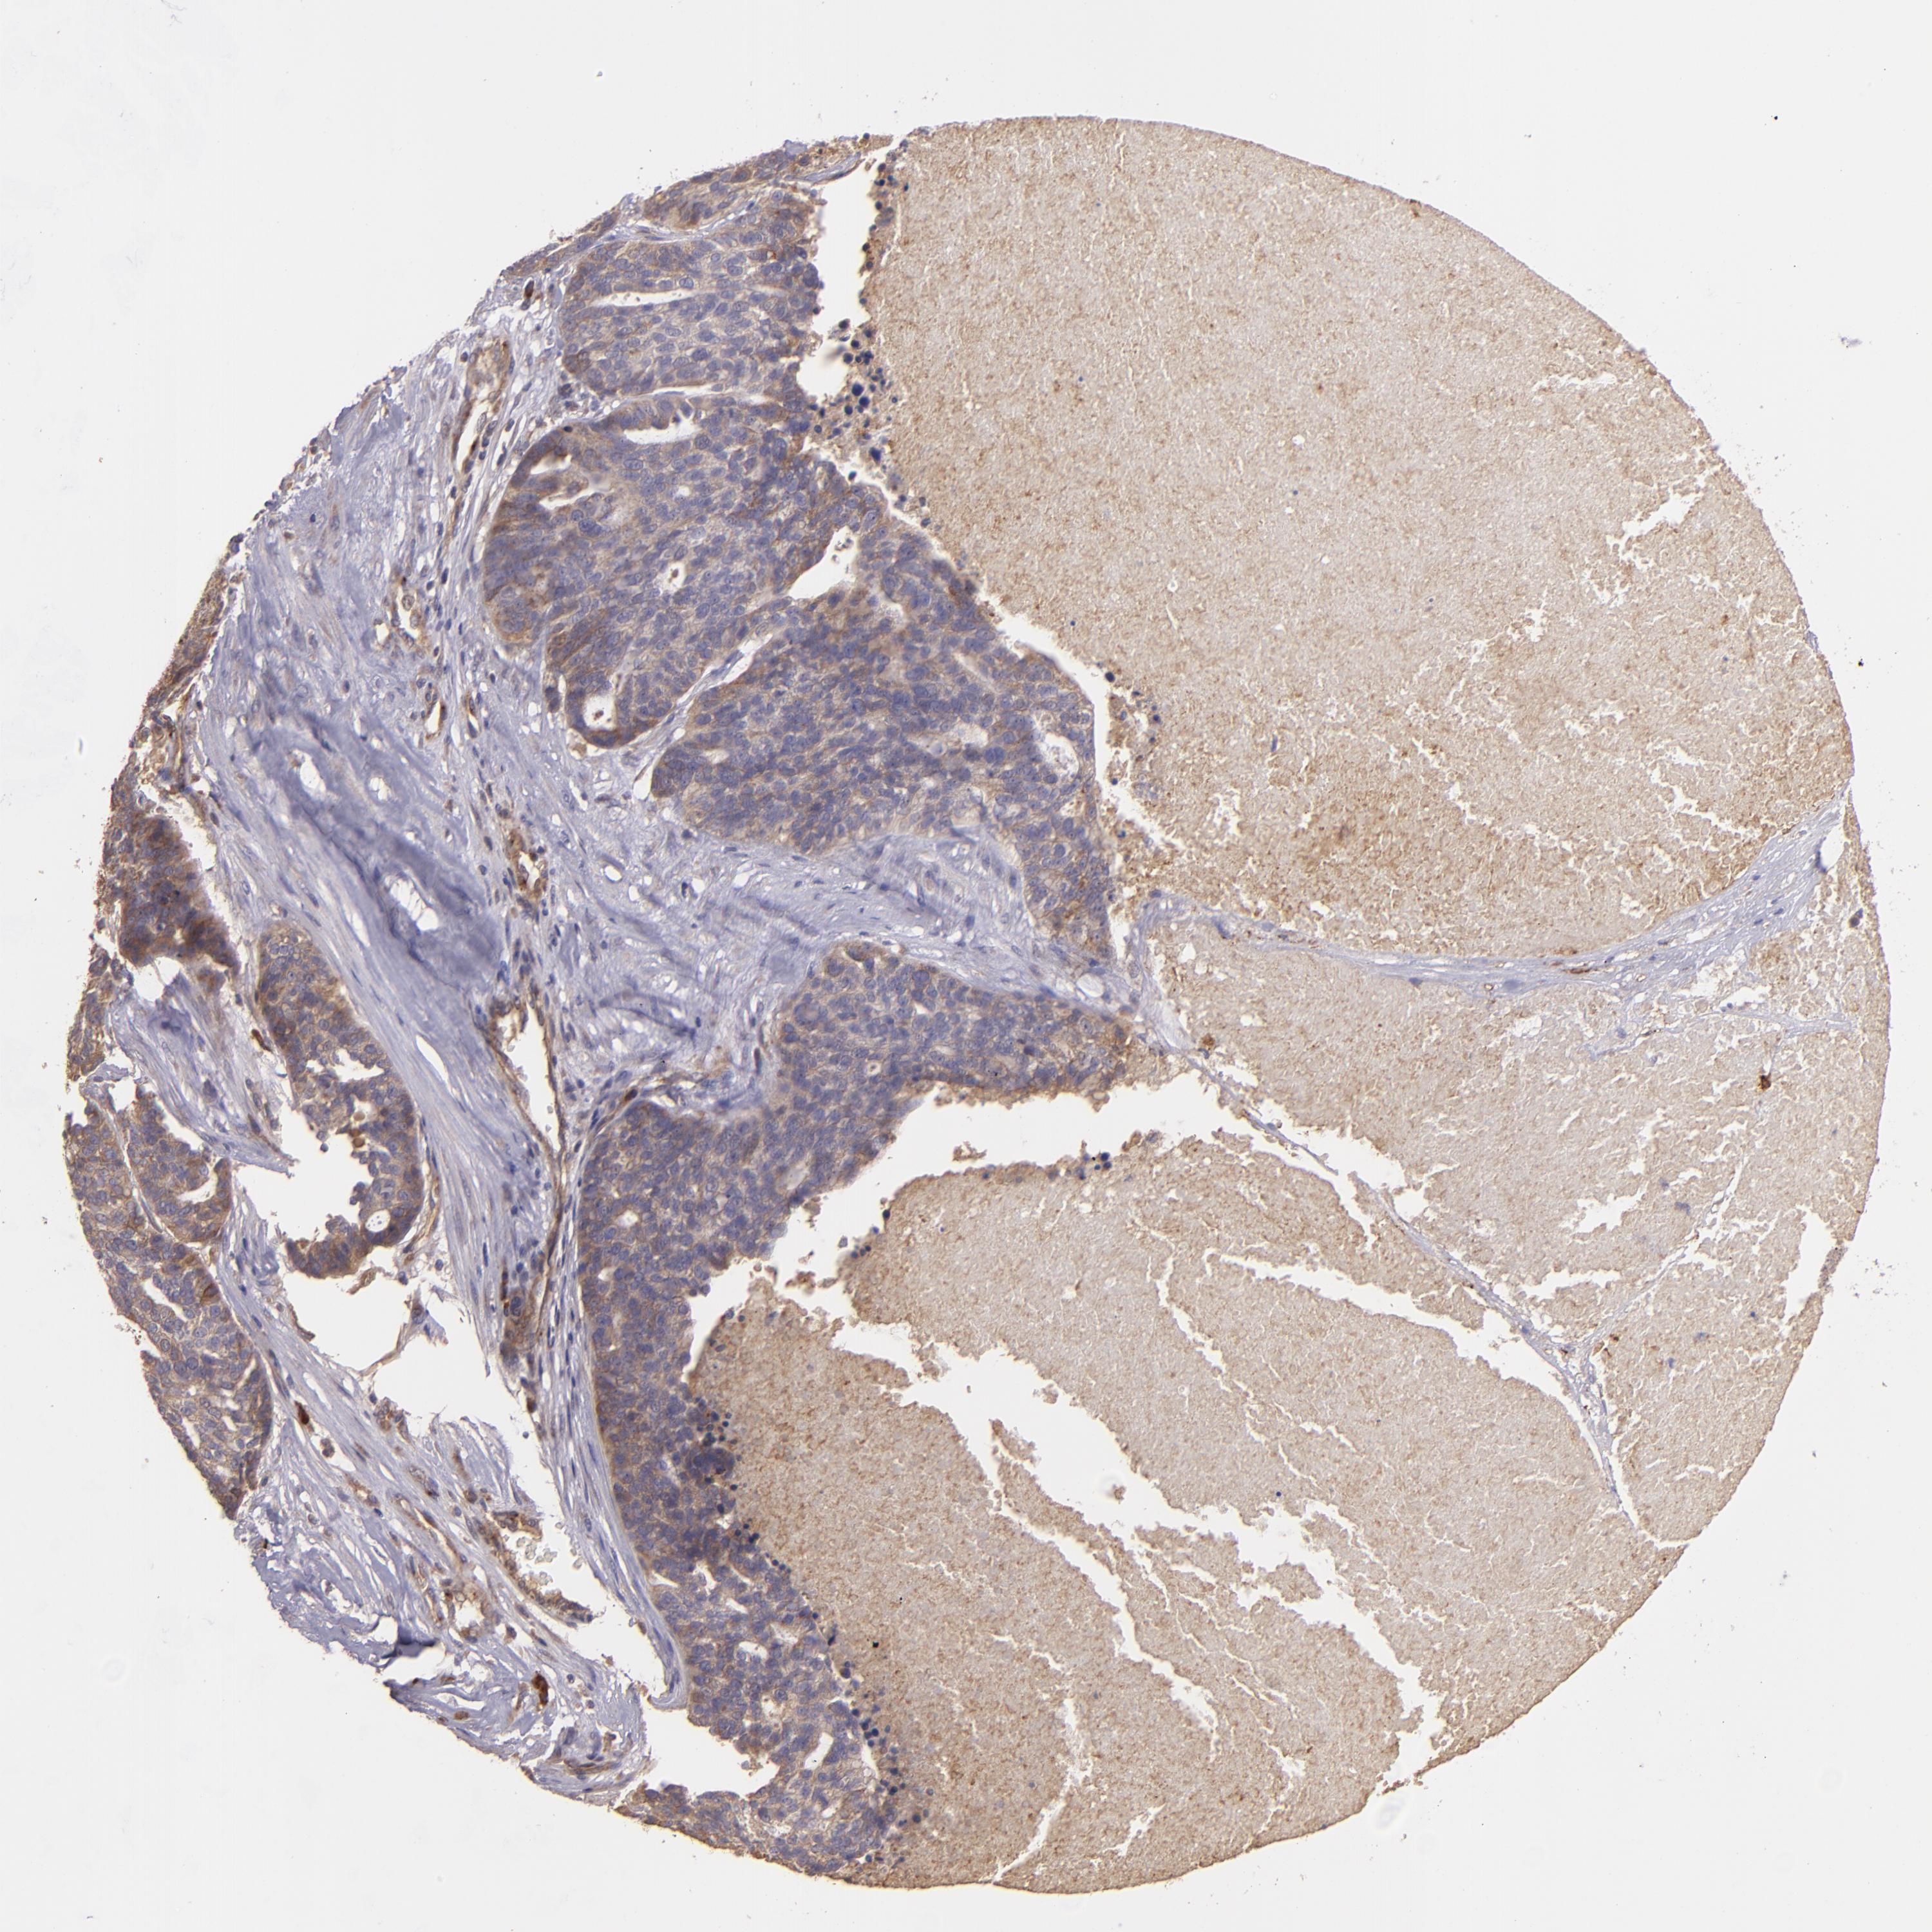

OVARIAN CANCER - Protein expressioni

A mouse-over function shows sample information and annotation data. Click on an image to view it in a full screen mode. Samples can be filtered based on level of antibody staining by selecting one or several of the following categories: high, medium, low and not detected. The assay and annotation is described here.

Note that samples used for immunohistochemistry by the Human Protein Atlas do not correspond to samples in the TCGA dataset.

Antibody stainingi

Antibody staining in the annotated cell types in the current human tissue is reported as not detected, low, medium, or high, based on conventional immunohistochemistry profiling in selected tissues. This score is based on the combination of the staining intensity and fraction of stained cells.

Each image is clickable and will lead to virtual microscopy that enables deeper exploration of all samples and also displays staining intensity scores, fraction scores and subcellular localization as well as patient and tissue information for each sample.

Antibody HPA013616

Cystadenocarcinoma, mucinous, NOS

Carcinoma, endometroid

Cystadenocarcinoma, serous, NOS

Carcinoma, NOS